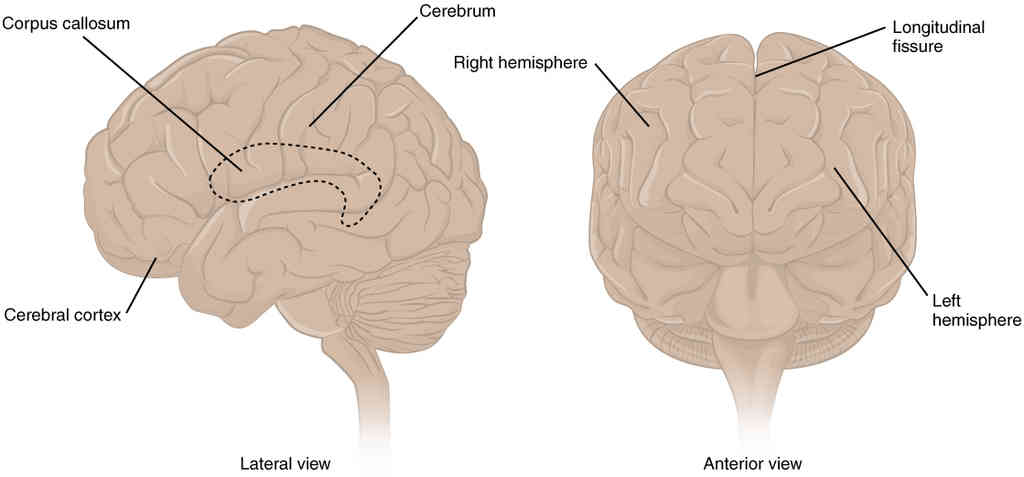

This page is under construction. For now, it is just a resource of the images found in the OpenStax Anatomy and Physiology Handbook. It wil slowly change into a revision tool. Each slide has a number. Use this to refer to the slide. When completed, it will have an unlabelled section, with labelled slides in parallel. On the unlabelled slides, write your answer and use the labelled slide to assess yourself. Keep track by also noting the number on each slide. Improvement at each attempt is important, more so than full marks on a first attempt.